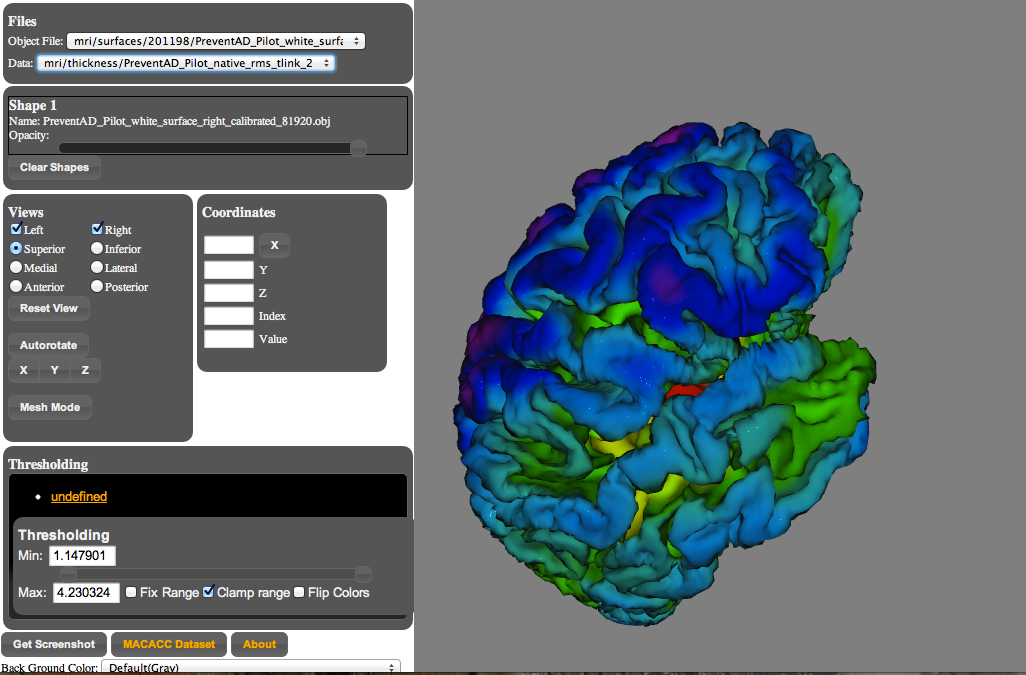

BrainBrowser

..a set of web-based 3D visualization tools primarily used for viewing neurological data i.e. MRI scans.

It allows for real-time manipulation and analysis of 3D neuroimaging data through any modern web browser. TRY ME!

BrainBrowser - 3D Surface Viewer